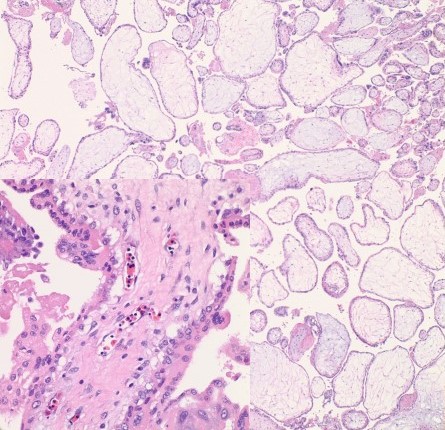

- Villi are small (size of 2-2.5 endometrial glands or <4 mm) (figure 1).

- Trophoblastic proliferation in polarized (trophoblasts grow in columns towards the oxygen source)

Exceptions: extrauterine (fallopian tube pregnancy) can show significant trophoblastic proliferation. This can be attributed to the more circumferential oxygen source in a very tight space and generally earlier gestational age in tubal pregnancies. (figure 2).